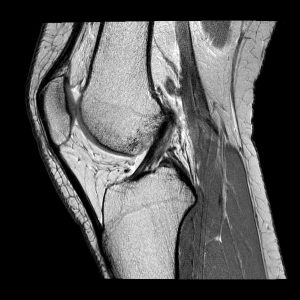

LCA RM